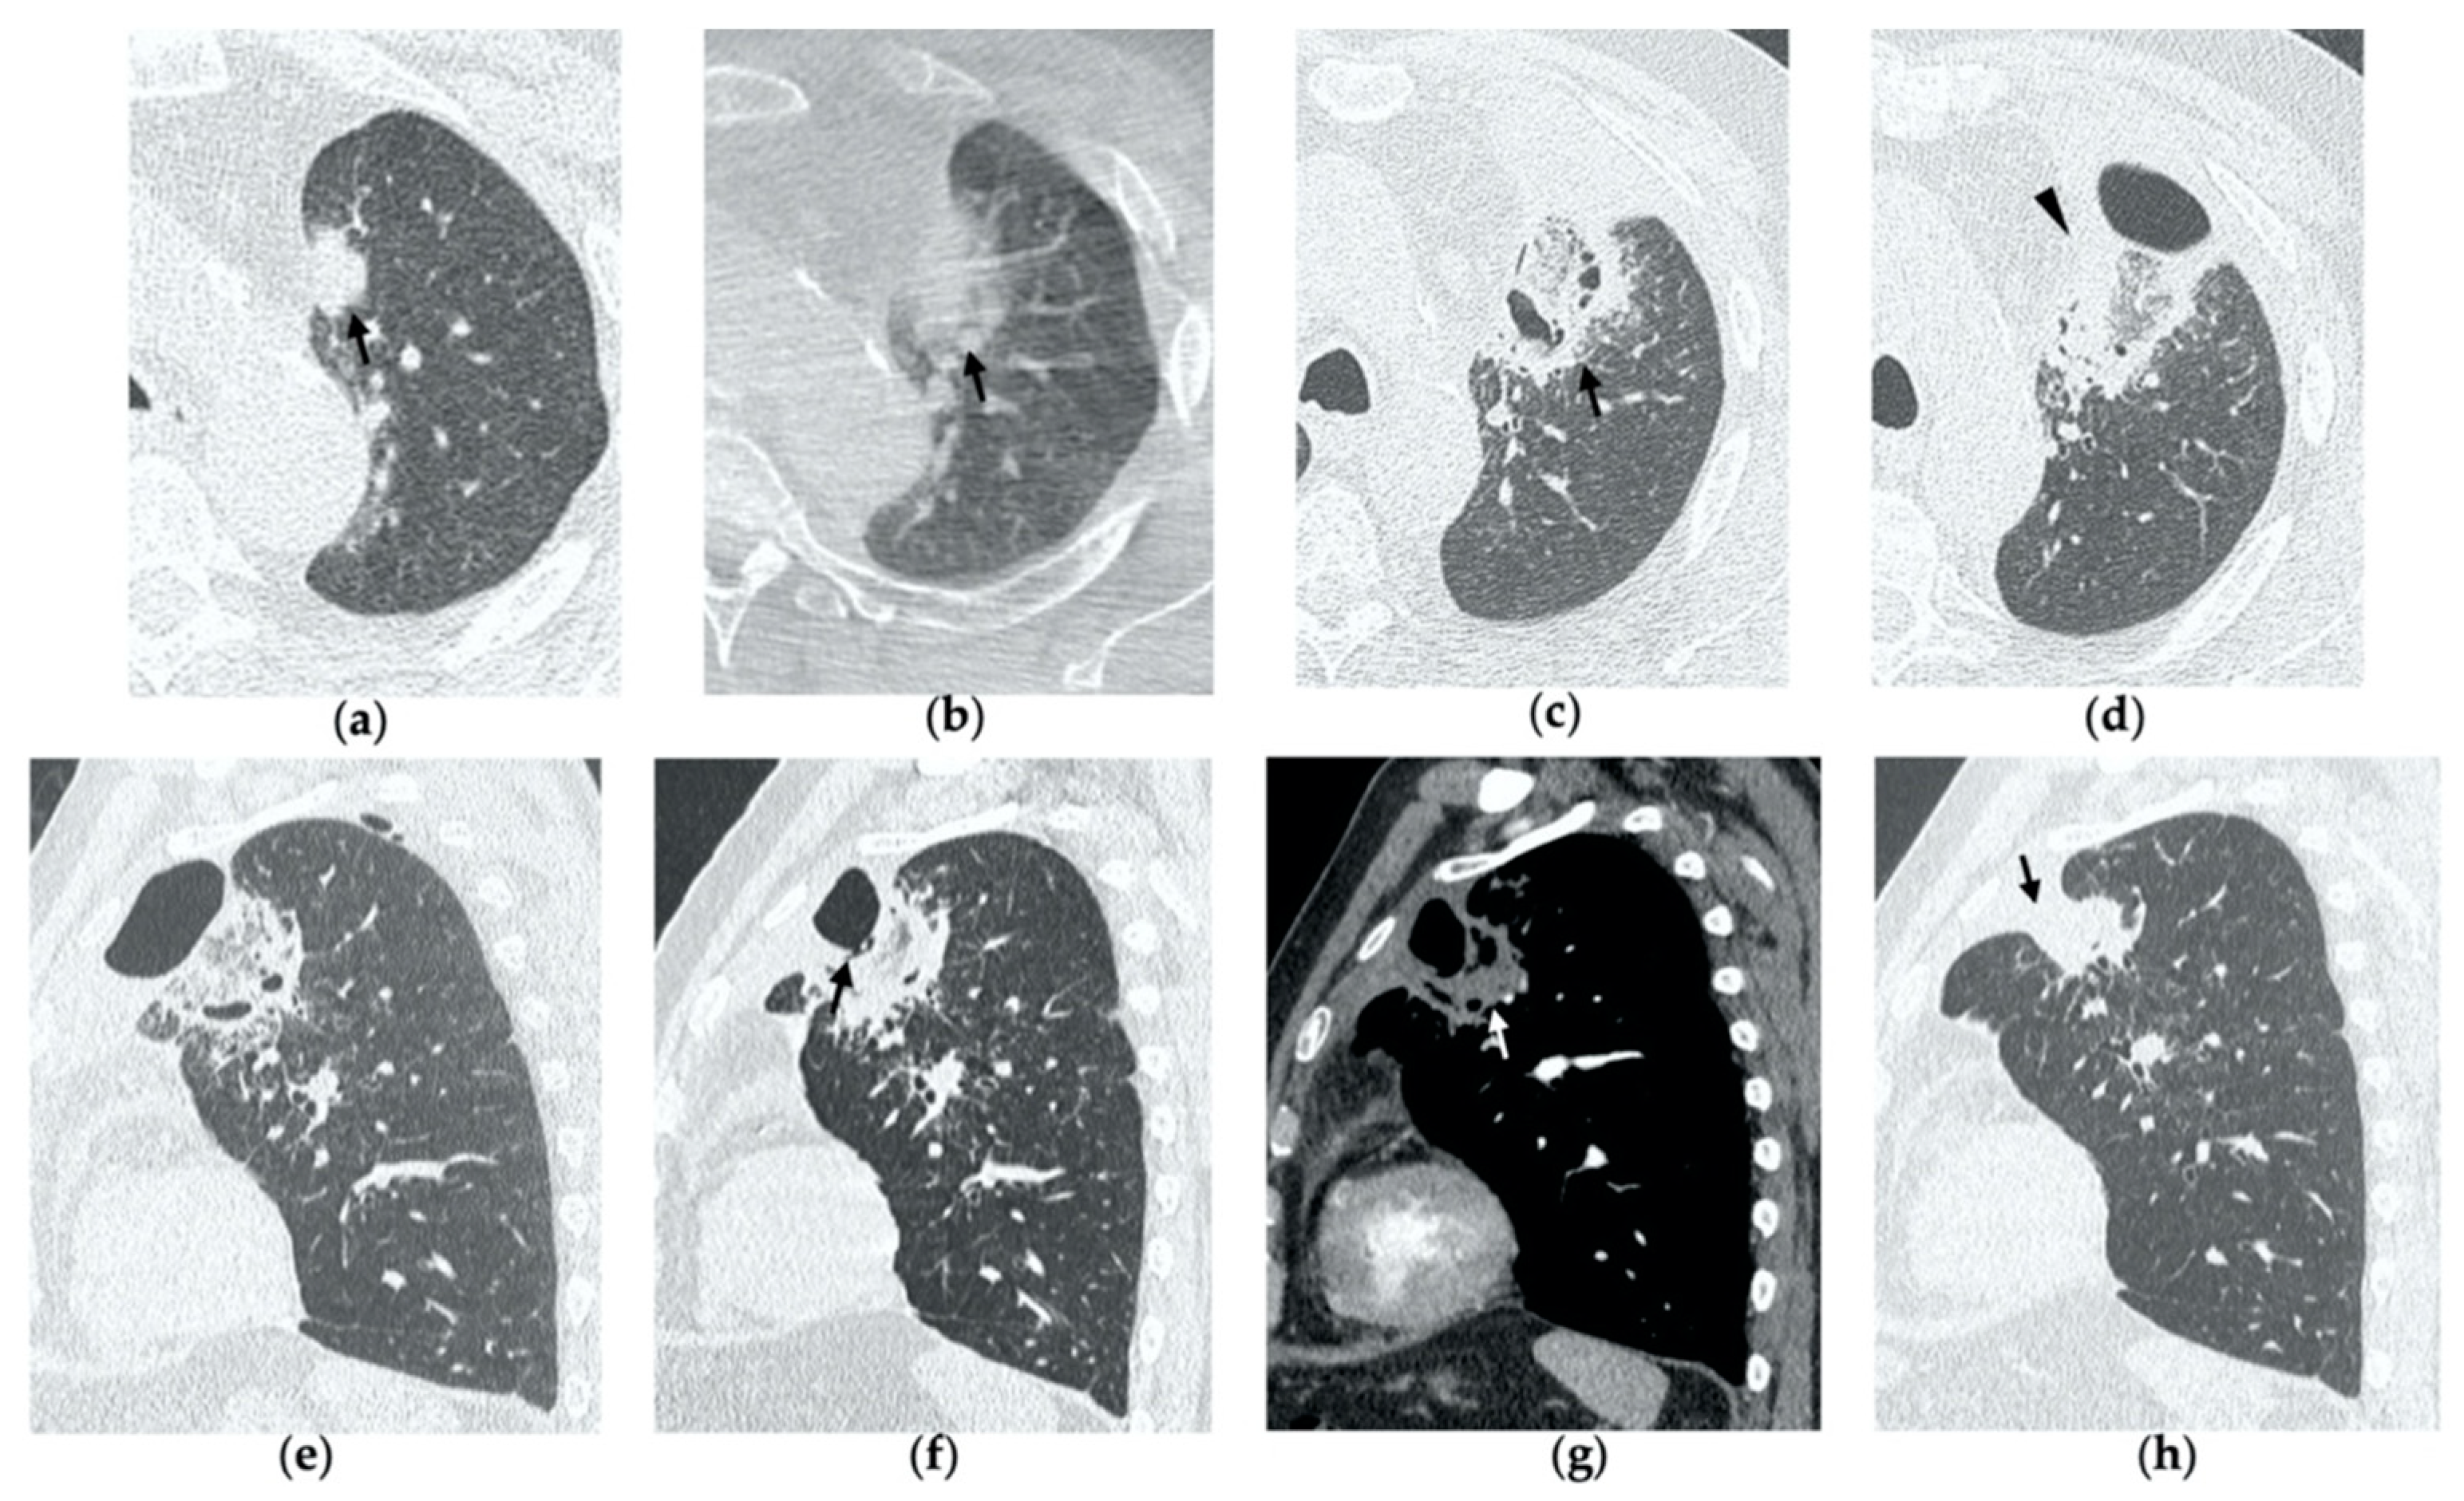

Figure 2. 69-year-old woman with a biopsy-proved NSCLC in the right upper lobe. (a) Pre-treatment axial CT. (b) Cone-beam CT image post-MWA shows GGO (black arrow) among the ablation site. (ce) Axial 1-month follow-up CT shows (c) a large consolidation with well-defined margins, inner hypoattenuating bubbles and a cavitation (black arrow) in communication with a peripheral bronchus (arrowhead); (d) on a different level, central necrotic material is seen within the cavitation (black arrow) (e) with no contrast enhancement (white arrow). (f,g) Axial 6-month follow-up CT images show resolution of the cavitation and decrease in size of the consolidation (black arrow) with no contrast material uptake (white arrow). (h,i) Axial 9-month follow-up CT image shows a linear fibrotic band with no contrast enhancement.

3.2. Contrast-Enhanced CT at 1 Month

By the first month after MWA, the rim of parenchymal GGO has dissolved in most patients as a result of regressing parenchymal edema, inflammation and hemorrhage, and the ablation site appears as an area of consolidation with a mean diameter still larger than the preablation zone (Figure 3c,d and Figure 4c,d) [21]. It is, therefore, crucial in this phase to measure the area of consolidation by its maximum axial diameter in order to thoroughly compare it during the following phases [7]. The consolidation may demonstrate inner cavitation or a central hypoattenuating area with reduction in contrast material uptake, along with a mild peripheral enhancement layer as an expression of reactive hyperemia, which should present smooth with linear margins (Figure 1c) [7,15]. This phenomenon must be referred to benign periablational enhancement and it should be differentiated from pathological contrast uptake, which is usually more irregular and nodular-shaped [7]. It is, therefore, pivotal to perform CT before and after contrast material administration in order to adequately evaluate the enhancement features of the treated tumor. The ablation site may also show hypoattenuating bubbles or a cavity with thin walls, containing solid tissue with reduced contrast enhancement, necrotic material or air-fluid levels, and a communication between the cavitation and a bronchus may be recognized (Figure 2c–e) [7,16]. The latter being a common finding since the necrotic tissue may be evacuated through a bronchus and it should not be mistaken for rare although possible complications, such as an abscess or a broncho-pleural fistula (BPF). Unlike the normal cavitary changes of the ablation area, an abscess is a rare complication (0.5%) [20] and appears as a cavity with thick walls, irregular internal contours and air-fluid level, and must be suspected when fever and laboratory signs of infection are present [22]. Pleural changes are also common findings, especially in peripheral lesions, including pleural thickening in the region of pleura traversed by the microwave antenna, pleural retraction and effusion [15]. Reactive mediastinal lymphadenopathy often occurs at an early stage, and it should not be considered a sign of tumor progression [7,23].

3.4. Contrast-Enhanced CT at 6 Months

After 6 months, the ablation site undergoes further involution and there should not be any inner contrast enhancement, except for the persistent benign periablational area (Figure 2f,g) [7]. The previously mentioned cavities decrease in size and may completely disappear. CT images may show fibrotic scarring without contrast enhancement and mild architectural parenchymal distortion of the surrounding lung (Figure 1f,g) [24]. At this stage, small treated nodules may already show a linear fibrotic evolution on CT images (Figure 2h,i).